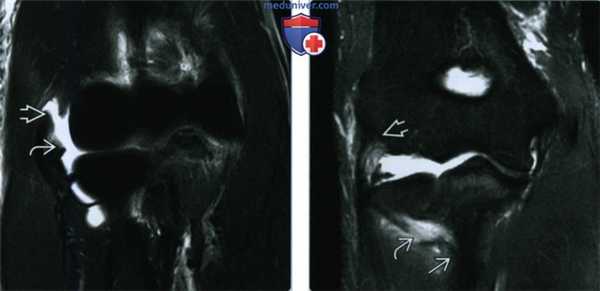

(Слева) На ультразвуком продольном снимке визуализируется лежащее сверху нормальное сухожилие сгибателя и сама мышца, однако ткань локтевой коллатеральной связки дезорганизованная и избыточная, что характерно для разрыва. Обратите внимание на выступающий бугорок и нормальную щель локтевого сустава.

(Справа) На продольном ультразвуковом снимке на этом же месте у этого же пациента при вальгусном сдавливании определяется патологическая щель в суставе, подтверждающая существенное растяжение локтевой коллатеральной связки и, вероятно, полный разрыв. (Слева) При сравнении с продольным ультразвуковым снимком у этого же пациента на противоположной стороне видны натянутые, интактные волокна локтевой коллатеральной связки, переходящие от медиального надмыщелка В к выступающему бугорку.

(Справа) На фронтальной МРТ Т2ВИ FS у подростка 16 лет после вывиха предплечья определяется полное разволок-нение локтевой коллатеральной связки без отчетливо видимых волокон в средней части связки. Визуализируется только дистальная культя. (Слева) На фронтальной МРТ Т2ВИ FS определяется отдельный разрыв переднего пучка локтевой коллатеральной связки в месте прикрепления к медиальному надмыщелку.

(Справа) На фронтальной МРТ Т1ВИ у этого же па -циента при такой же локализации среза видно, что разрыв локтевой коллатеральной связки вызван отрывом небольшого костного отломка от плечевой кости. Отрывы зачастую лучше распознаются на Т1ВИ в связи с лучшими отличительными свойствами сигнала костного мозга. В таких случаях полезным дополнением является рентгенография.